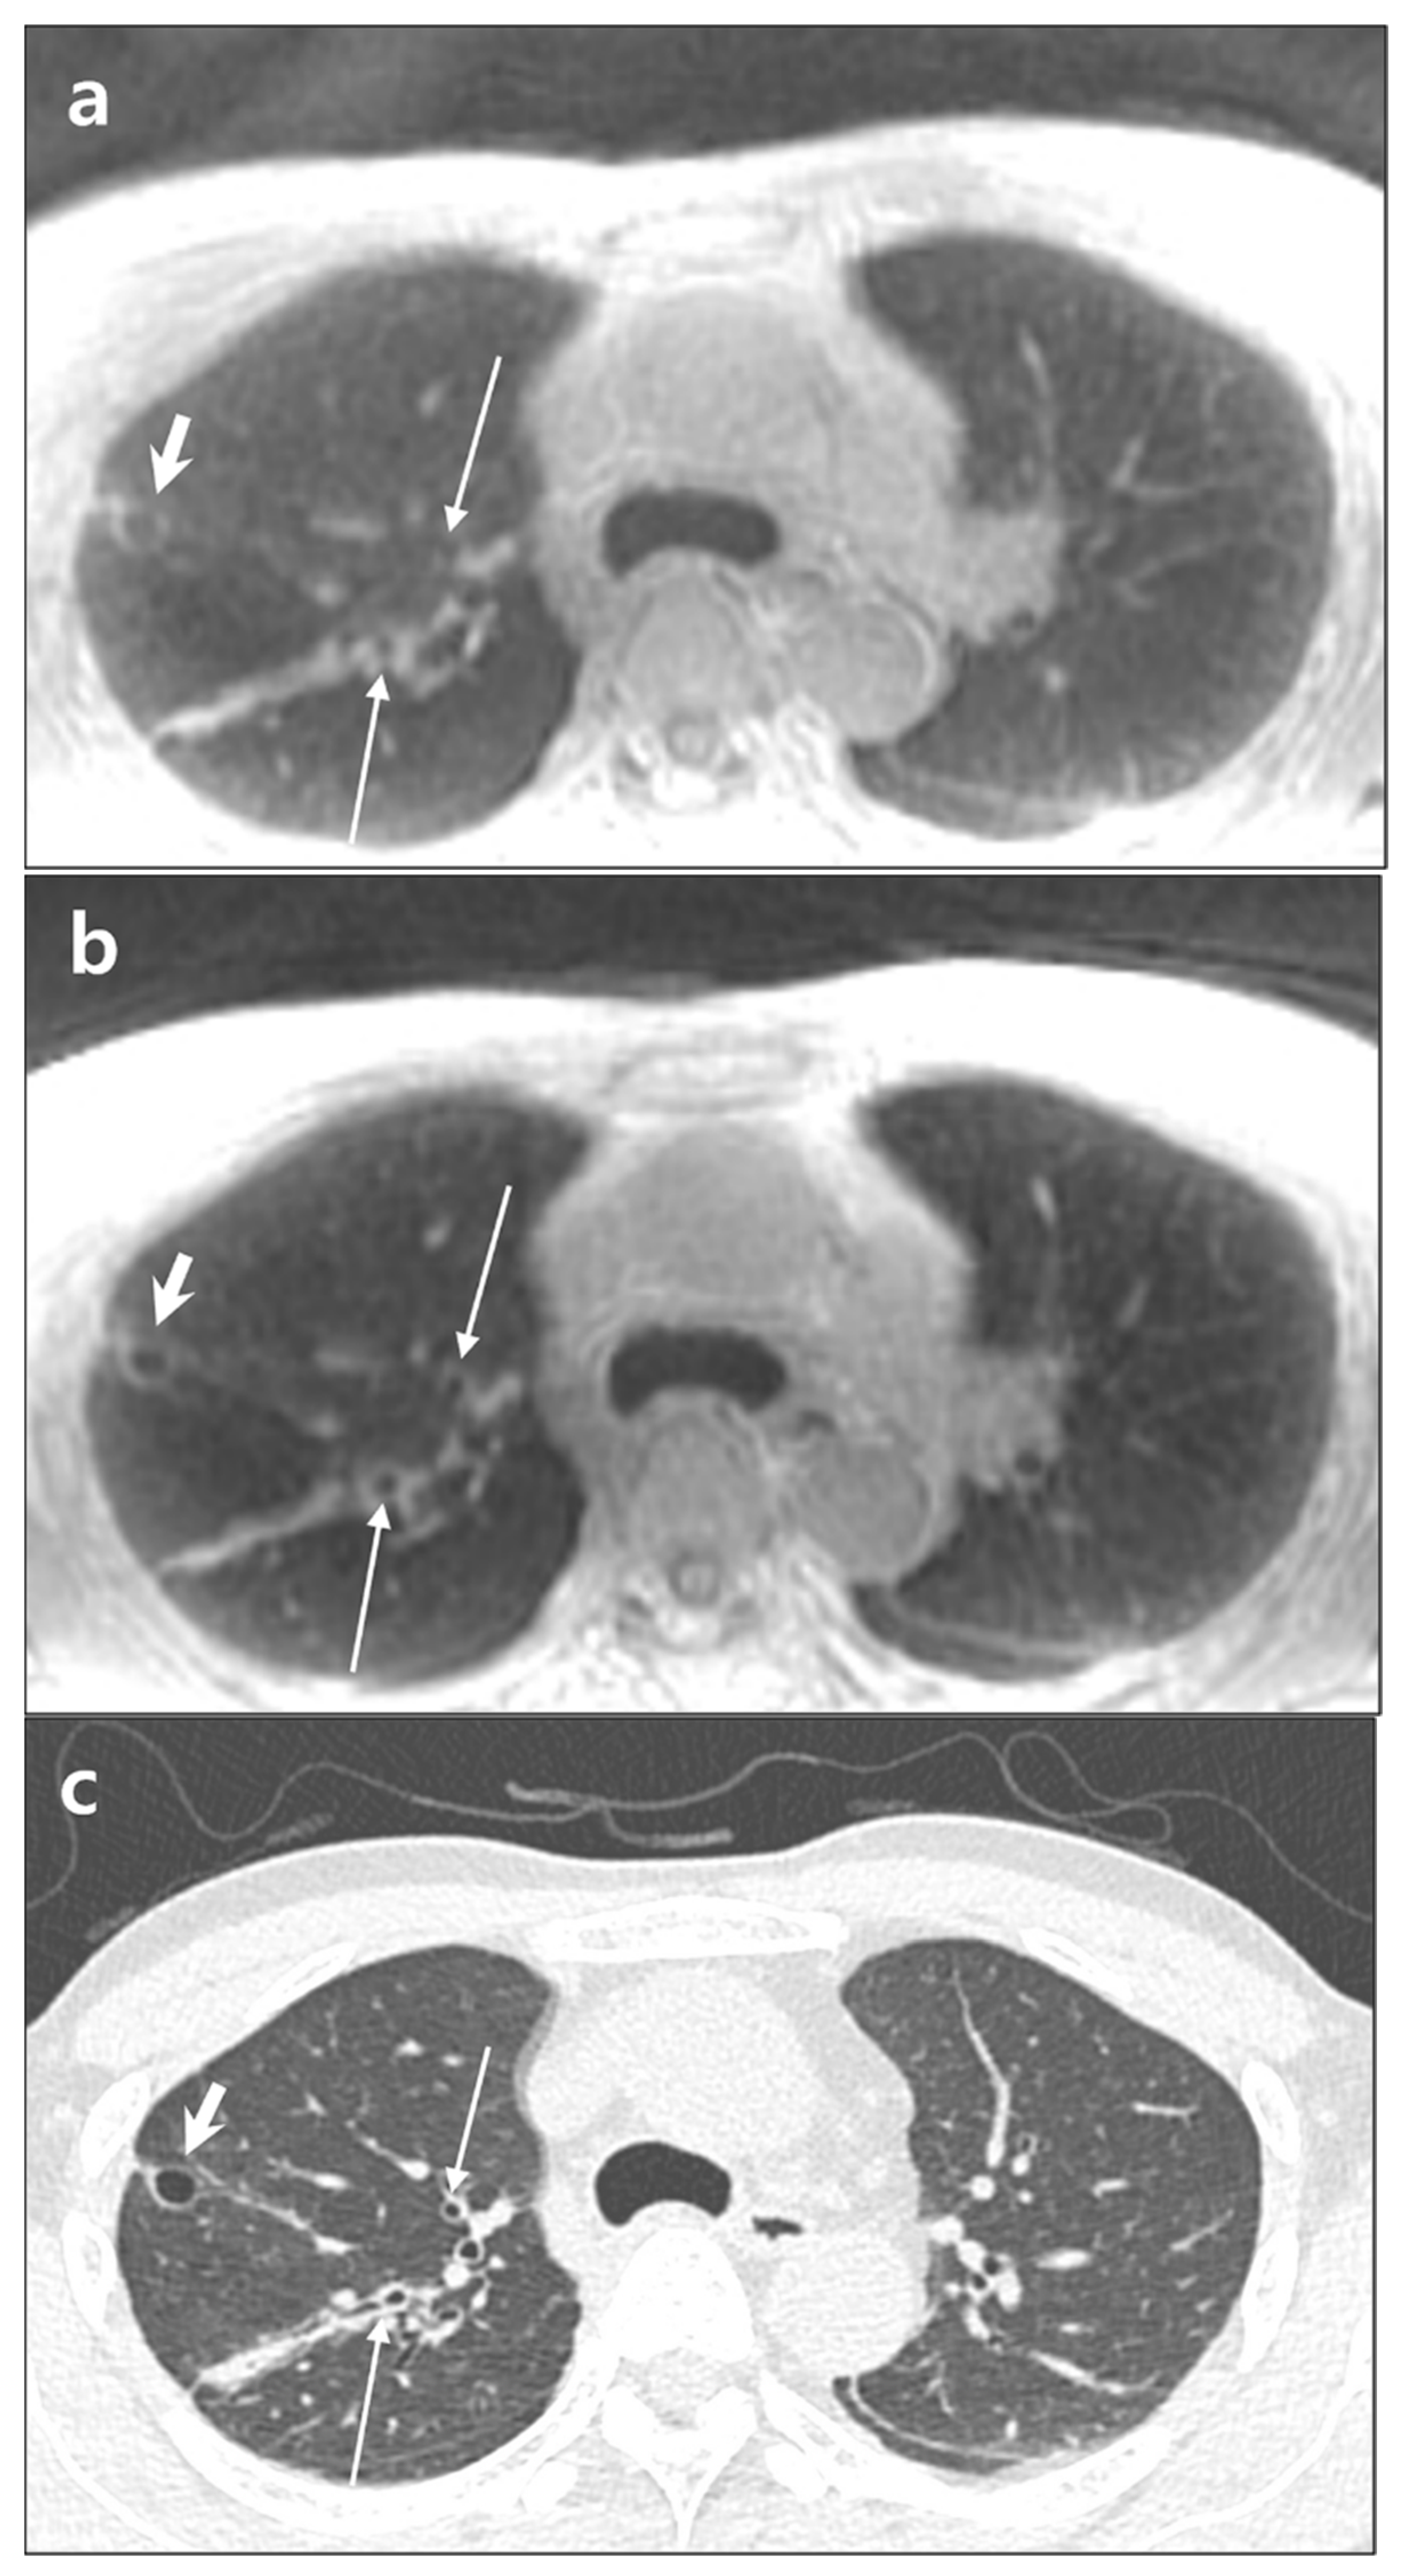

3.3. Lesion Detection